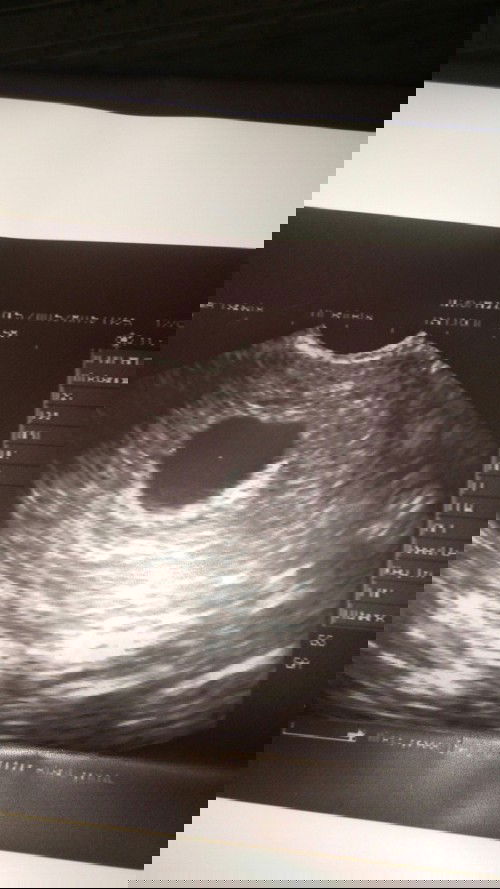

Hi mga momsh sino po dito yung kada may mararamdamang masakit sa puson o kaya spotting, o kaya kahit panaginip lang ay super para noid na yung kung anu anu na iniisip na baka mag ka totoo yung dreams mo, about sa baby mo sa tummy mo kaya nag spotting ka tas sumakit puson mo kung anu anu na pumapasuk sa isip mong hindi maganda. na baka ganito oh ganyan na baka may mangyaring masama sa baby mo sa loob ng tummymo na kahit sabihin ng oby its normal peru nakaka pag alala lang kasi first baby namin to ni hubby and syempre tagal naming hinintay to. #firstbaby #pregnancy